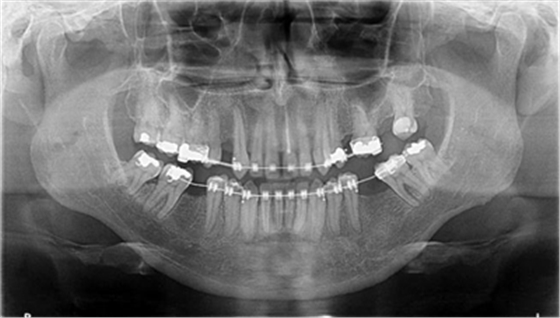

圖4a.病例2在正畸排齊后的臨床和放射學(xué)檢查。曲面斷層片顯示,在最初排齊后,雙側(cè)缺失的下頜第一磨牙以及近中傾斜的第二和第三磨牙,計(jì)劃在缺牙區(qū)進(jìn)行種植修復(fù)

圖4b.骨增量術(shù)前即刻臨床檢查和PAO 程序顯示,右下第一磨牙部分無(wú)牙牙槽嵴的寬度為7mm,左下第一磨牙近遠(yuǎn)中距離8mm。同時(shí)發(fā)現(xiàn)無(wú)牙區(qū)的牙槽嵴明顯吸收

經(jīng)過(guò)最初1年的正畸排齊后,右側(cè)下頜第一磨牙無(wú)牙區(qū)的近遠(yuǎn)中距離由6mm增至7mm,左側(cè)下頜第一磨牙的近遠(yuǎn)中距離由7mm增至8mm(圖4)。取得患者知情同意后,采用與病例1中描述的相同技術(shù)和材料進(jìn)行同期牙槽嵴增量和加速磨牙直立程序(圖5a-5g)。除了右側(cè)磨牙后區(qū),在右側(cè)第二和第三磨牙根部之間也進(jìn)行了去皮質(zhì)術(shù)(圖5d)。骨增量術(shù)后,即刻將0.016×0.022 英寸帶有30° 后傾彎的鈦鉬合金絲(Dentsply)置于兩側(cè)。6周后,以半個(gè)托槽的距離進(jìn)行主弓絲套推簧雙側(cè)輕加力(圖5h)。